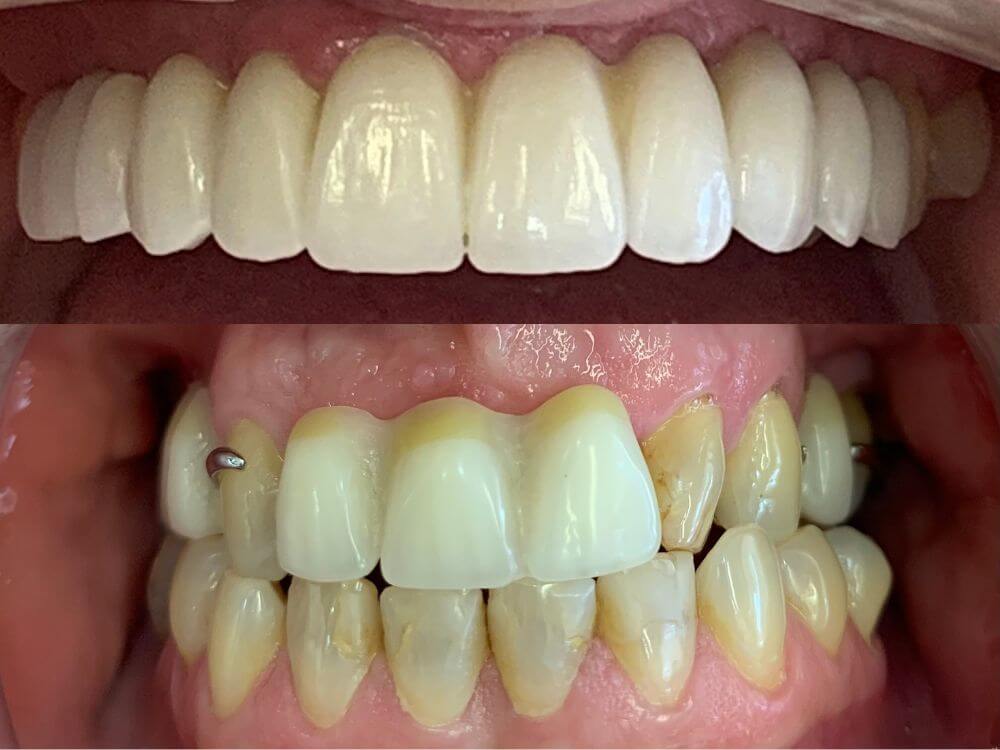

A melhor solução para quem perdeu um único dentes. Procedimento simples e rápido. Muito utilizado em casos de fraturas dentárias e tratamentos estéticos.

Tratamento que exige um planejamento altamente eficaz em casos complexos. Visa a reposição de múltiplos dentes perdidos utilizando implantes dentários.

Com o tempo, a ausência de um dente não substituído pode causar o desalinhamento de toda a arcada dentária. Além disso, uma reabilitação oral inadequada pode resultar em problemas estéticos e de fala, podendo até acentuar o aparecimento de rugas faciais ao longo do tempo.